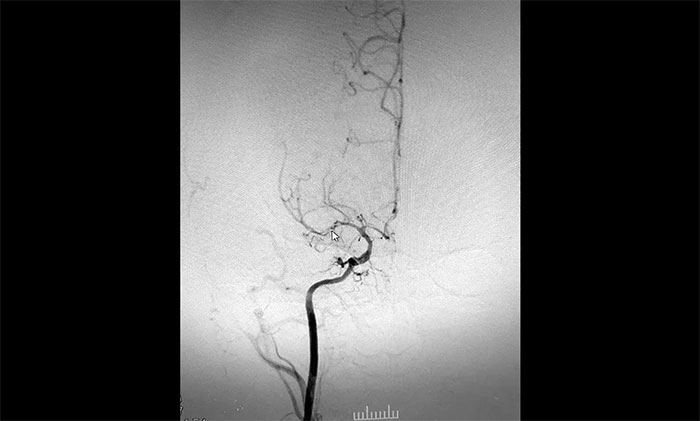

入院后,趙先生的DSA(腦血管造影)檢查再次明確“煙霧病”表現(xiàn):雙側(cè)大腦中動脈主干管腔纖細(xì)、分支細(xì)小;周圍代償性小血管網(wǎng)建立;右側(cè)頸內(nèi)動脈C3-4段纖細(xì),顯影毛糙;兩側(cè)頸內(nèi)動脈C4-6段鈣化形成伴管腔輕—中度狹窄。

▲DSA異常血管造影圖

神經(jīng)外科團(tuán)隊(duì)綜合DSA檢查結(jié)果和患者癥狀表現(xiàn),進(jìn)行了科學(xué)、審慎的評估。于耀宇主任談到,患者雙側(cè)頸內(nèi)動脈虹吸部和大腦中、前動脈主干近段明顯狹窄、近乎閉塞,異常血管網(wǎng)形成。雙側(cè)大腦半球多發(fā)供血區(qū)灌注不足,尤以右側(cè)缺血較為明顯。